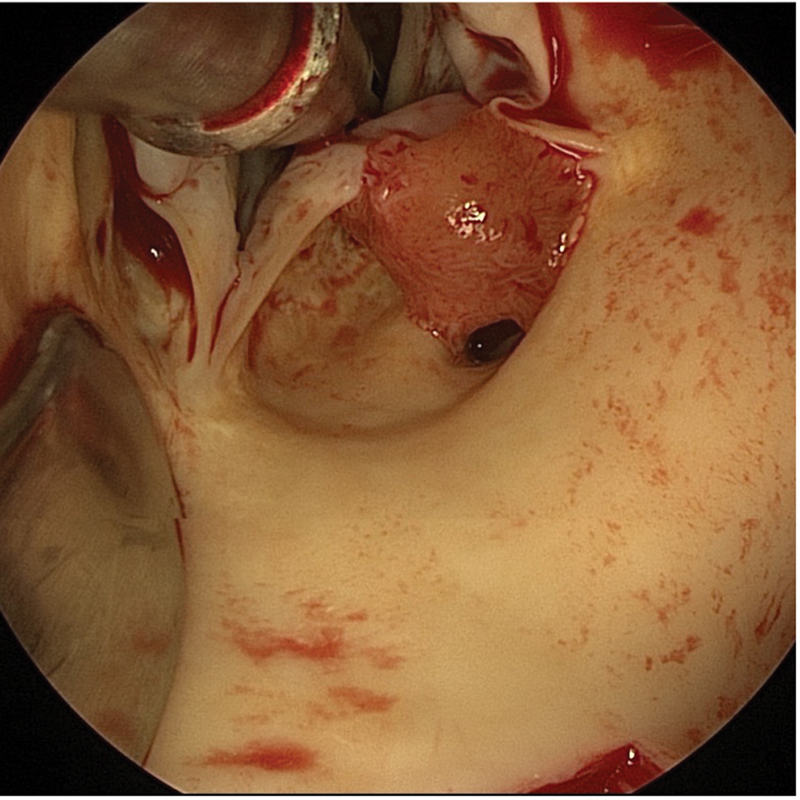

Symptoms of papillary fibroelastomas are often related to thromboembolic events but are rarely caused by a mechanical impairment of blood supply by the tumor itself. We describe a case of a papillary fibroelastoma in a 91-year-old female patient leading to a cardiac arrest through intermittent occlusion of the left coronary artery.

Abstract Image